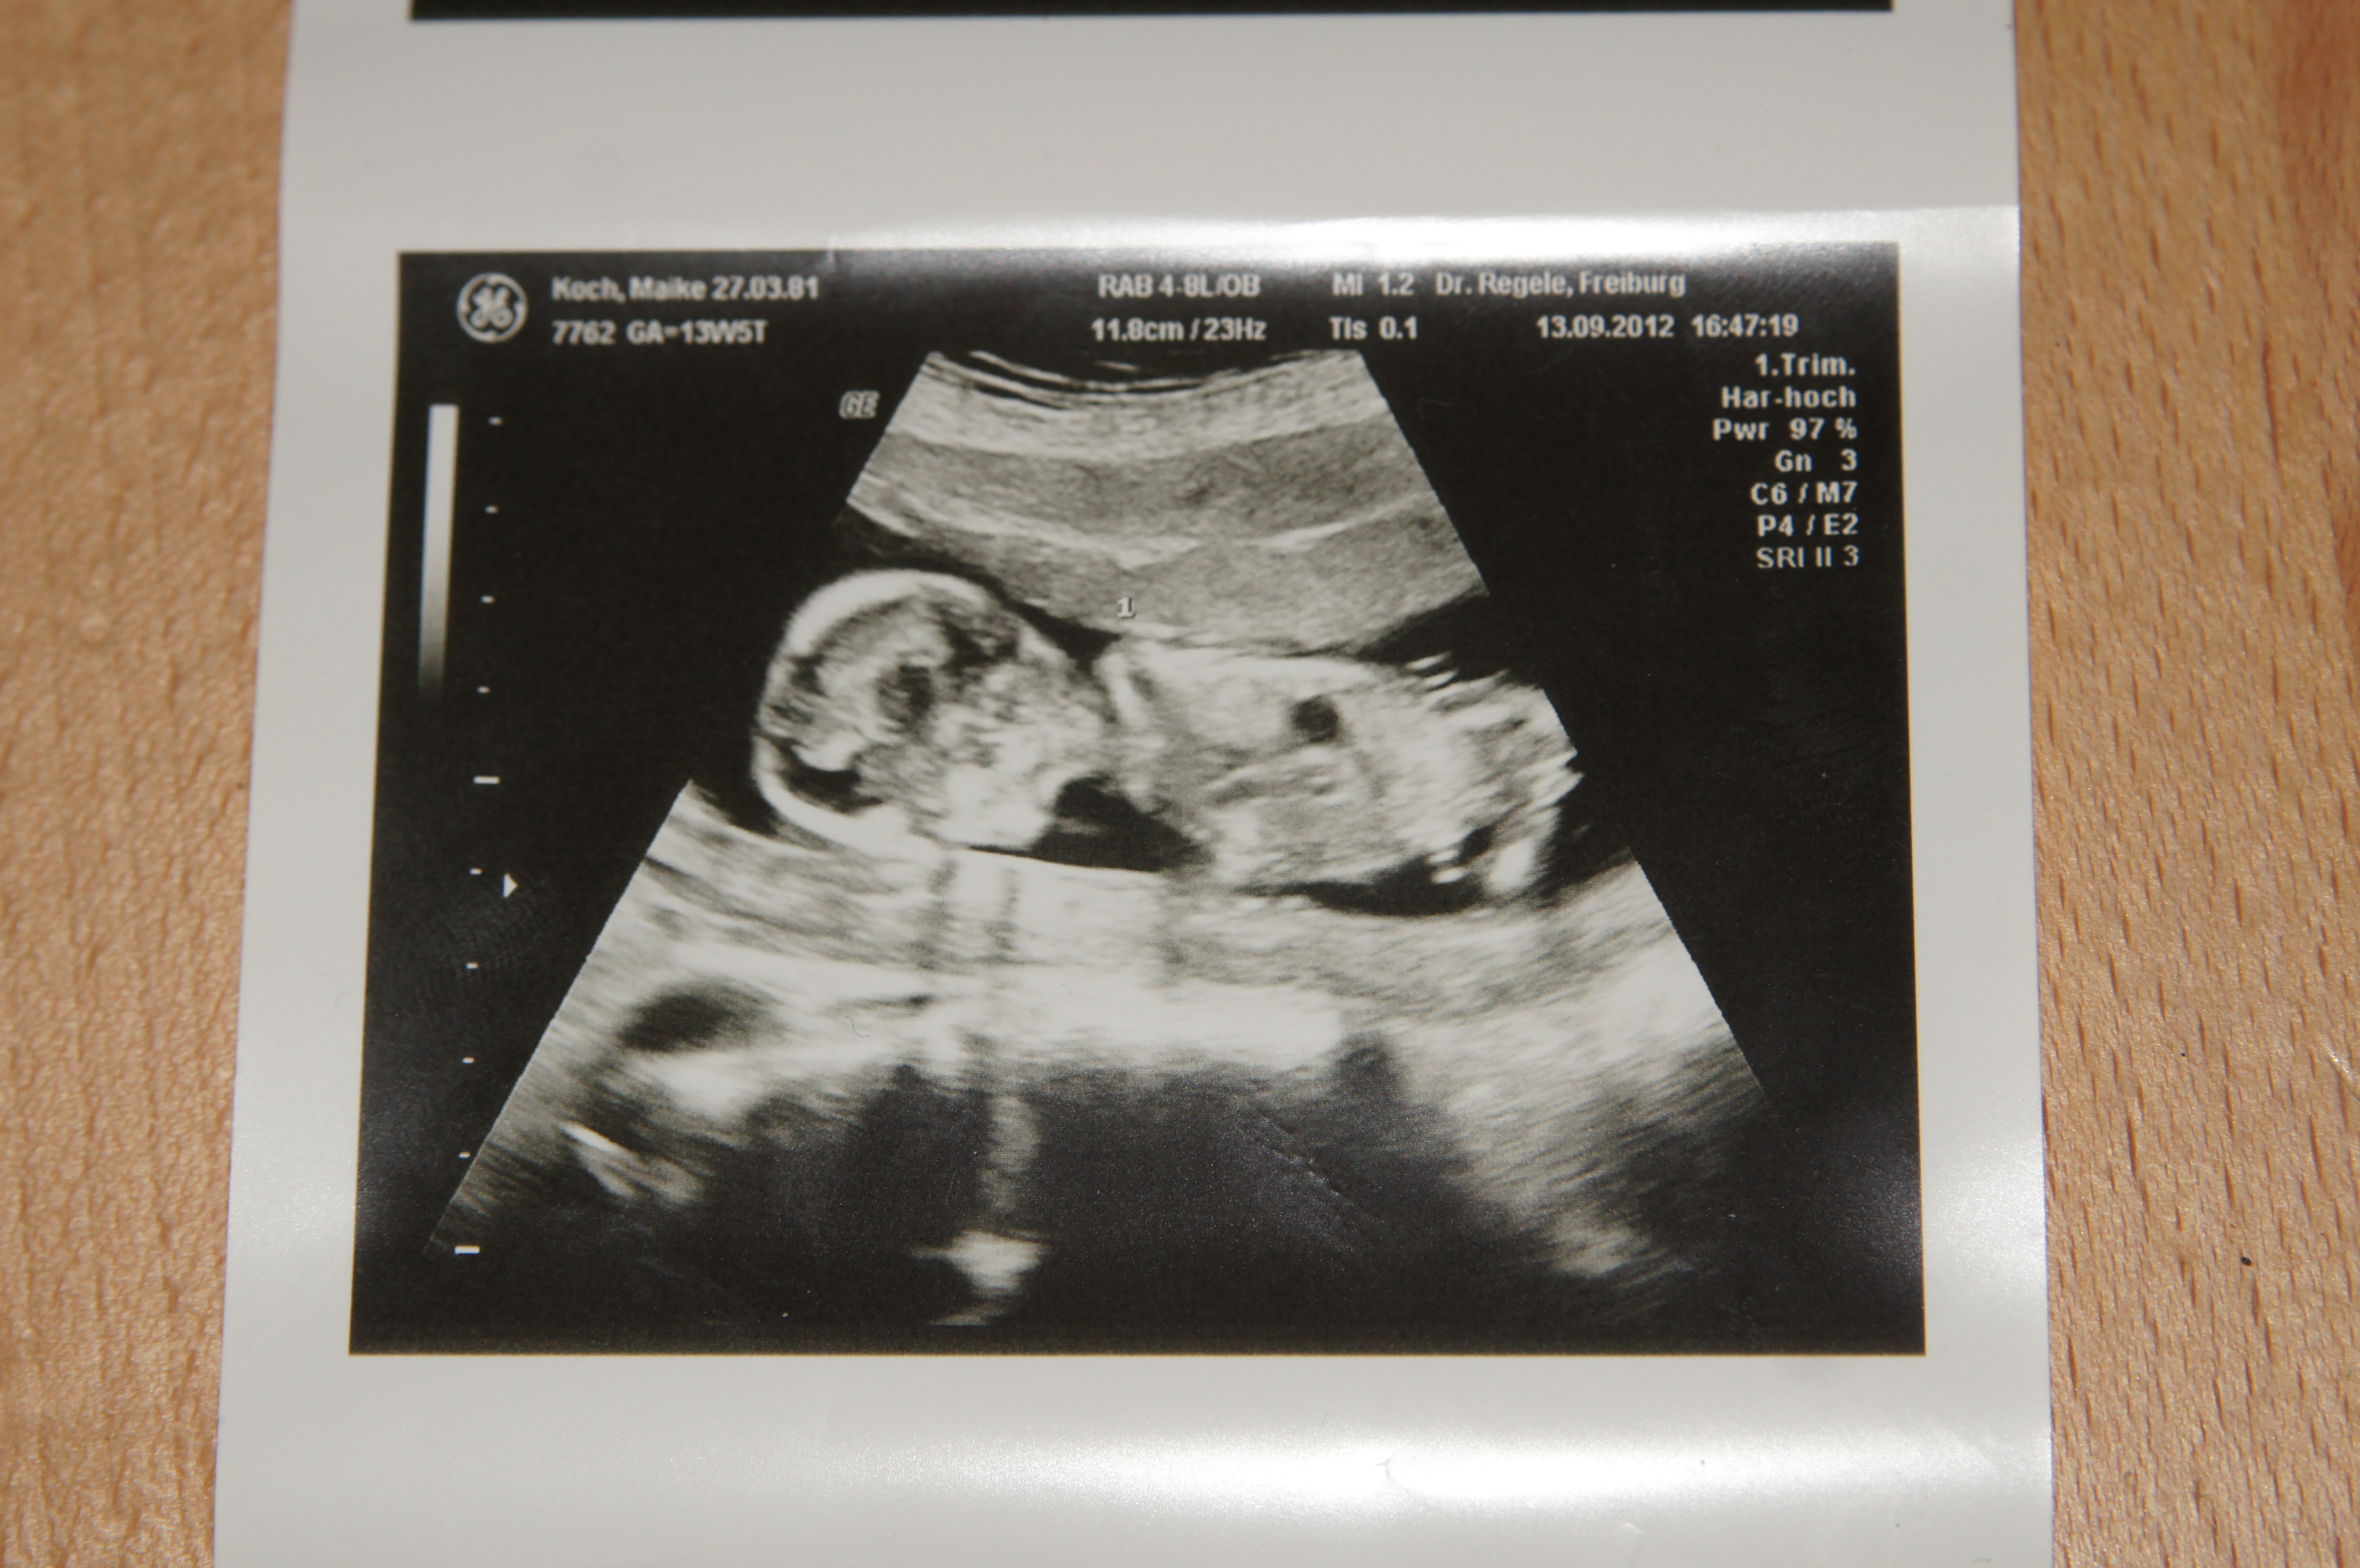

I am not sure baby is in a good position. I don't see anything. Sorry I'm not an expert though. Congrats